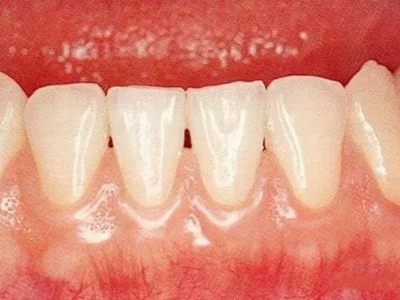

牙龈退缩露出淡黄色牙根图

牙龈退缩患者的牙龈退缩后,淡黄色牙龈明显露出。若进一步发展,易使对应位点的牙槽骨发生骨吸收,可能诱发龋齿、牙龈敏感、菌斑堆积等。